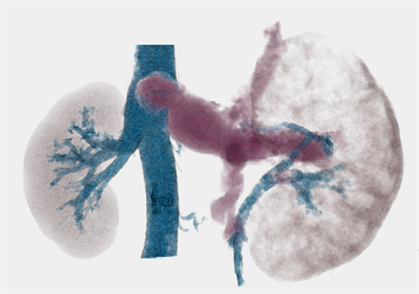

A 47-year-old man was referred to our institute with an enlarging left RCC. Computed tomography scanning revealed a large enhanced mass in the left kidney (Figure 1(a)) and local extension into the infrahepatic IVC (Figure 2) with pulmonary tumor embolism (Figure 3(a)). The embolism was located at the proximal portion of the right pulmonary artery, with no suspicious lesions in the left lung. As the mass of the RCC had been rapidly increasing in size for the past 2 months, early surgery was scheduled.

Figure 2. Computed tomography scan showing local extension of the left renal tumor into the infrahepatic inferior vena cava (white arrow heads).